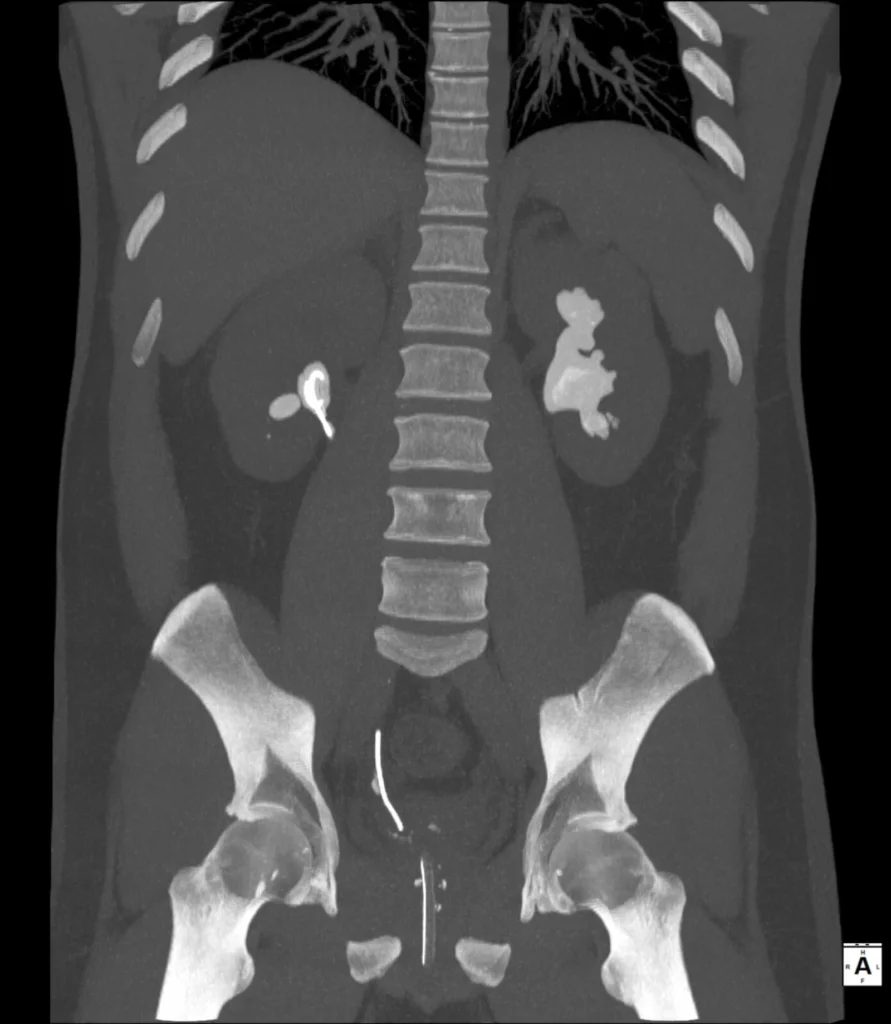

TC abdomen sin medio de contraste. MPR que muestra el extenso “molde” calicopielico a izquierda. Otras liatiasis en pelvi sy calices inferiore a derecha.

La tomografía computarizada sin contraste es el método de elección para la evaluación de la litiasis urinaria en el contexto de cólico renal. Permite confirmar la naturaleza cálcica de las lesiones, determinar su extensión dentro del sistema colector y valorar posibles complicaciones asociadas, como obstrucción o dilatación pielocalicial. Las reconstrucciones multiplanares facilitan la apreciación de la configuración coraliforme y su compromiso bilateral.

La correlación entre radiografía simple y TC resulta especialmente ilustrativa desde el punto de vista docente: mientras la radiografía permite sospechar el diagnóstico por la densidad y la morfología de las calcificaciones, la tomografía confirma con precisión su localización anatómica y extensión.